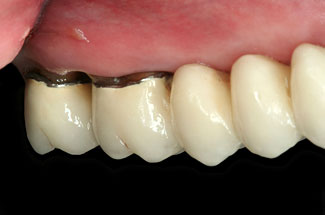

Abbildungen 3-5: Die klinischen Fotographien zeigen den Zustand nach der ersten professionellen Zahnreinigung.

Der komplexe Fall Der komplexe Fall

Abb. 3

Abb. 4